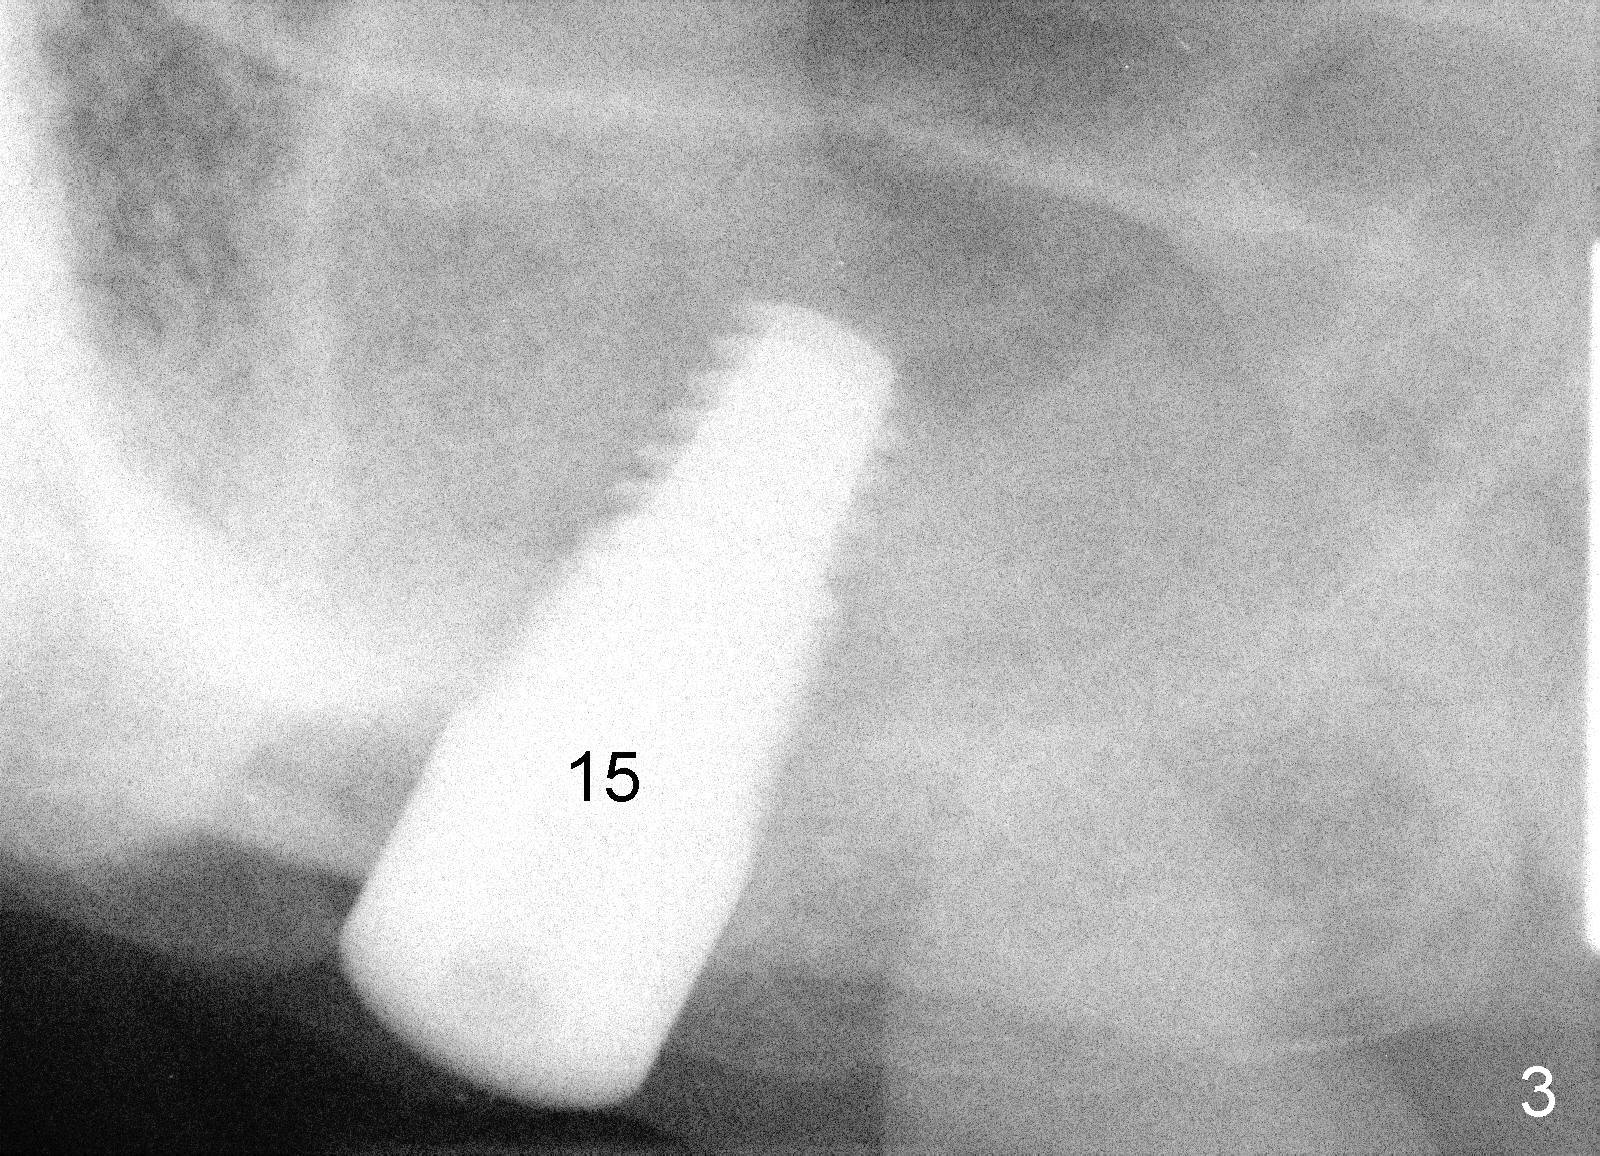

Mr. Tsang has a loose bridge (Fig.1: #13-15). The affected tooth (#15) was extracted two months ago. Immediate implant was placed (Fig.2: 4.5x17 mm tapered drill; Fig.3: 7x17 mm implant). It appears that the implant at the site of #15 must be somewhat parallel to the tooth #13, according to the trajectory of the drill in Fig.2.

Today an implant was placed at the site of #14. The trajectory turned out to be not great. How can we place it parallel to #13 and #15?